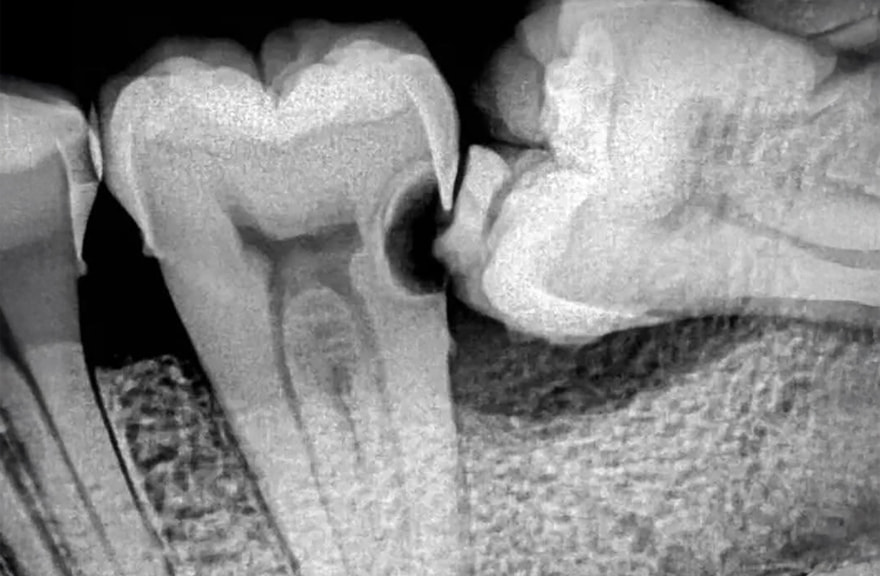

深刻なむし歯の原因になります

親知らずの影響で磨けない場所ができることがあります。

特に深刻なのは歯の深い部分のむし歯を作りやすいことです。深い部分の虫歯は非常に治療しにくく、頑張って治しても痛みや再発が生じやすいのです。親知らずは隣の大切な歯を失う原因になるのです。清掃不良を招く親知らずは、むし歯を作ってしまう前に、抜歯することをおすすめしています。

- 親知らずが横向き・斜めに生えており、隣の歯を圧迫している

- 親知らずの影響で、隣の歯に深い歯周ポケットができている